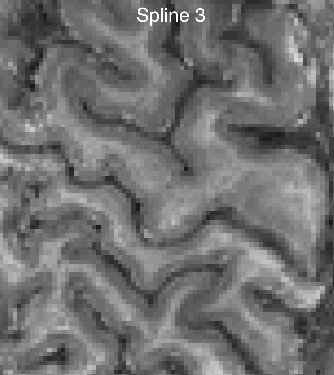

Strategy 4: Using an appropriate spatial interpolation algorithm

The spatial resampling can be done with multiple interpolation algorithms. Most popular might be: Nearest Neighbor, linear, and spline. To my surprise, resampling with a linear interpolation is much to blurry for its popularity.

My personal advise is to refrain from interpolation methods of Nearest-Neighbor or “linear” and use a higher order splines instead.